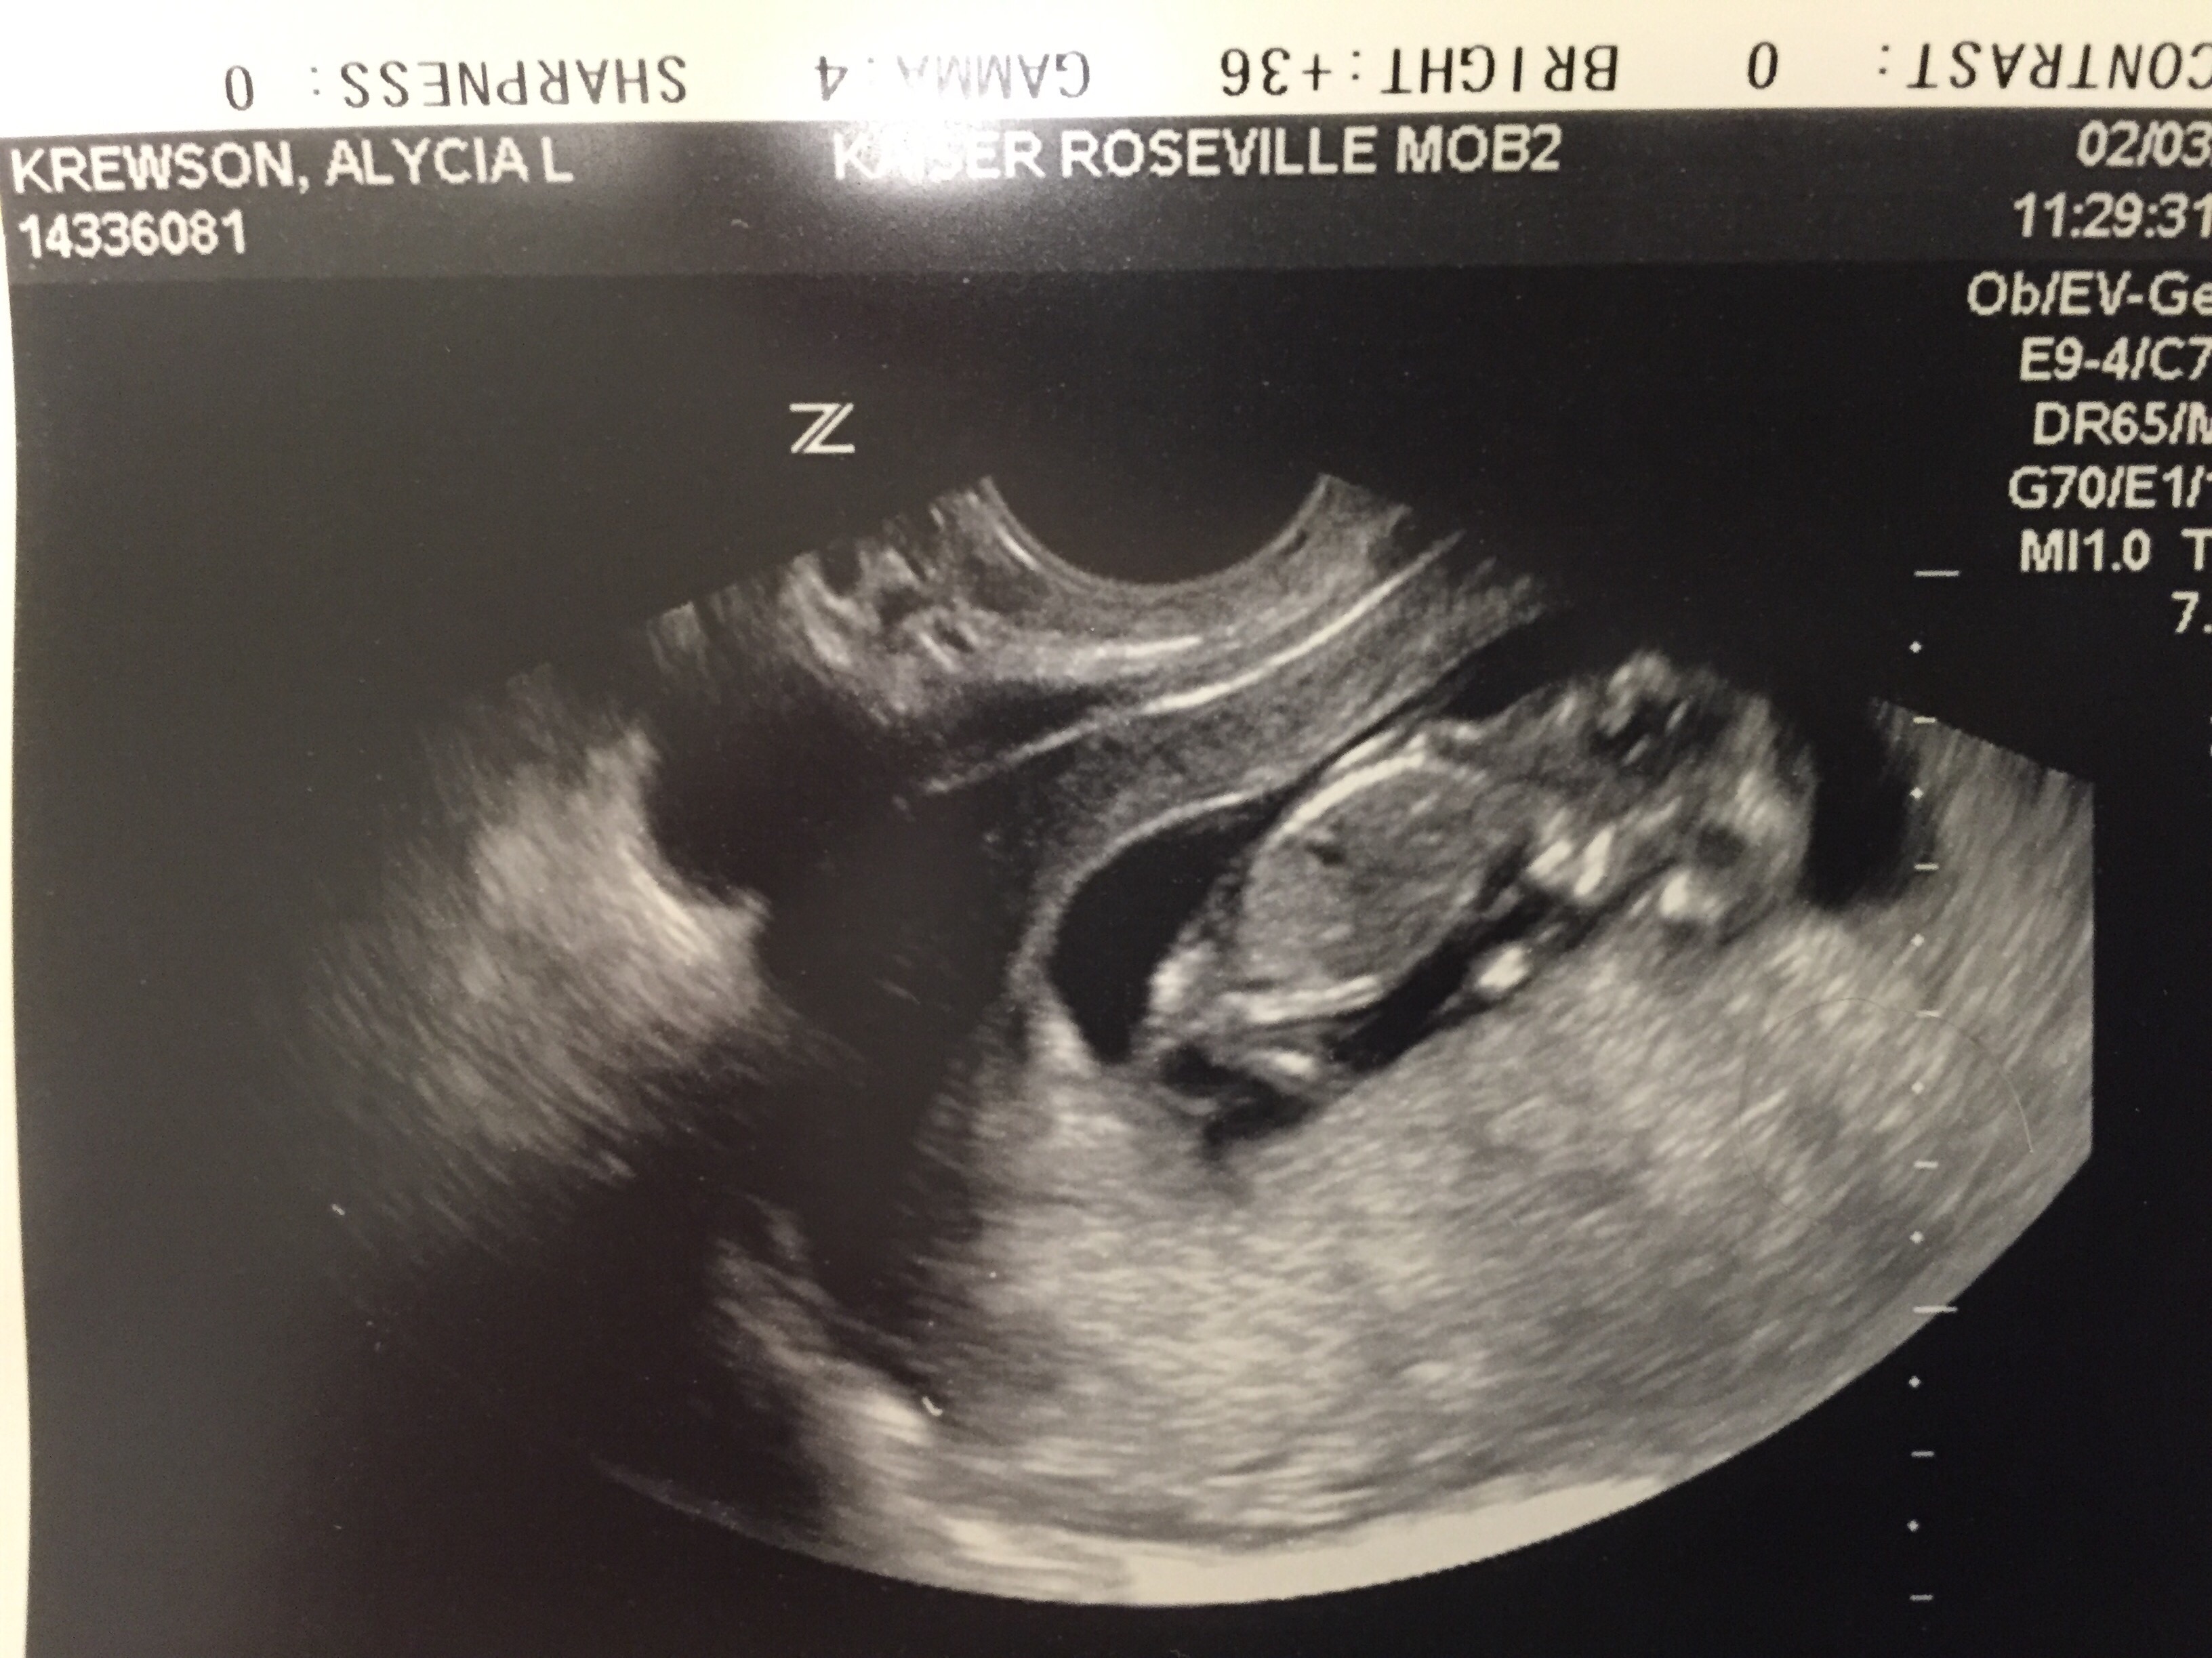

Can anyone tell if my baby is a Boy or Girl??! Ultrasound is from today! I'm 11w5d! :)

• I'm assuming this was a transabdominal ultrasound. Soooo I'd guess a boy :) although I know it's too early to really tell, I think the Ramzi theory is fun anyways!

• I do not see a nub in this picture to be able to tell, but if you go after 12 weeks it is usually pretty accurate!

• @akrews, You realize your personal information is all over that photo, right?

I also would suggest you reconsider paying for an ultrasound at 14 weeks. I wouldn't trust the results that early. I'd be slightly more comfortable at 16 weeks, but even then is still borderline early. I know you're excited and anxious, but there's a reason that most scans where they can predict sex are scheduled around 18-20 weeks (even though that's not the purpose of the scan).

• You can easily tell the gender at 14 weeks if you go to an experienced sonographer with the right equipment. We went to the same place this time as we did with our son, and it was very obvious both times the sex of the baby by 14 weeks. With my son he could tell within 2 seconds, with this one it took about 5 minutes to get a clear shot and see the 3 lines.